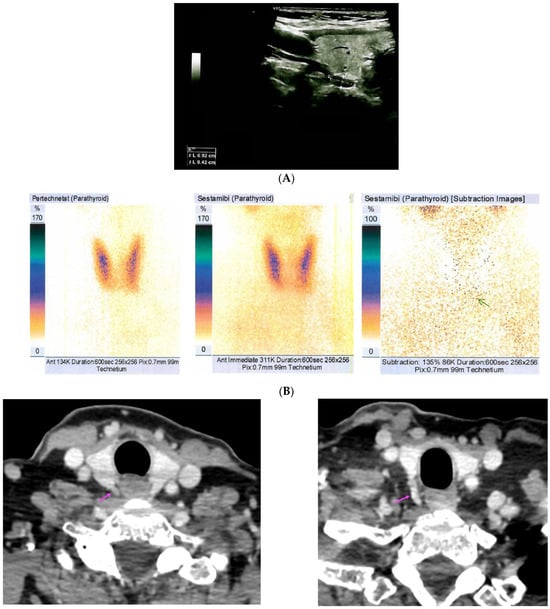

Background: Adding subtraction single-photon emission computed tomography/computed tomography (SPECT/CT) to dual isotope (I-123 and Tc-99m-sestamibi) subtraction parathyroid scintigraphy is not widely implemented. We aimed to assess the added value of dual isotope subtraction SPECT/CT over single isotope SPECT/CT as an adjunct to dual [...] Read more.

Background: Adding subtraction single-photon emission computed tomography/computed tomography (SPECT/CT) to dual isotope (I-123 and Tc-99m-sestamibi) subtraction parathyroid scintigraphy is not widely implemented. We aimed to assess the added value of dual isotope subtraction SPECT/CT over single isotope SPECT/CT as an adjunct to dual isotope planar pinhole subtraction scintigraphy. Methods: Parathyroid scintigraphies from 106 patients with an estimated total of 415 parathyroid glands who (1) were diagnosed with primary hyperparathyroidism, (2) underwent dual isotope subtraction scintigraphy in the Department of Nuclear Medicine, Gentofte Hospital, Denmark throughout 2017 and (3) underwent subsequent parathyroidectomy, were included. The original dual isotope planar pinhole subtraction plus dual isotope subtraction SPECT/CT (dual/dual method) exams were retrospectively re-evaluated using only Tc-99m-sestamibi SPECT/CT (dual/single method). Statistics were calculated per parathyroid. Surgical results confirmed by pathology served as reference standard. Results: The dual/dual method had higher sensitivity than the dual/single method (82% (95%CI 74%–88%) vs. 69% (95%CI 60%–77%)) while specificity, positive and negative predictive values (PPV and NPV) were similar (specificity 96% vs. 93%, PPV’s 87% vs. 82% and NPV’s 89% vs. 93%). Reader confidence was higher when employing the dual/dual method (p = 0.001). Conclusions: The dual/dual method can be considered superior to the dual/single method in the preoperative imaging in primary hyperparathyroidism. Full article